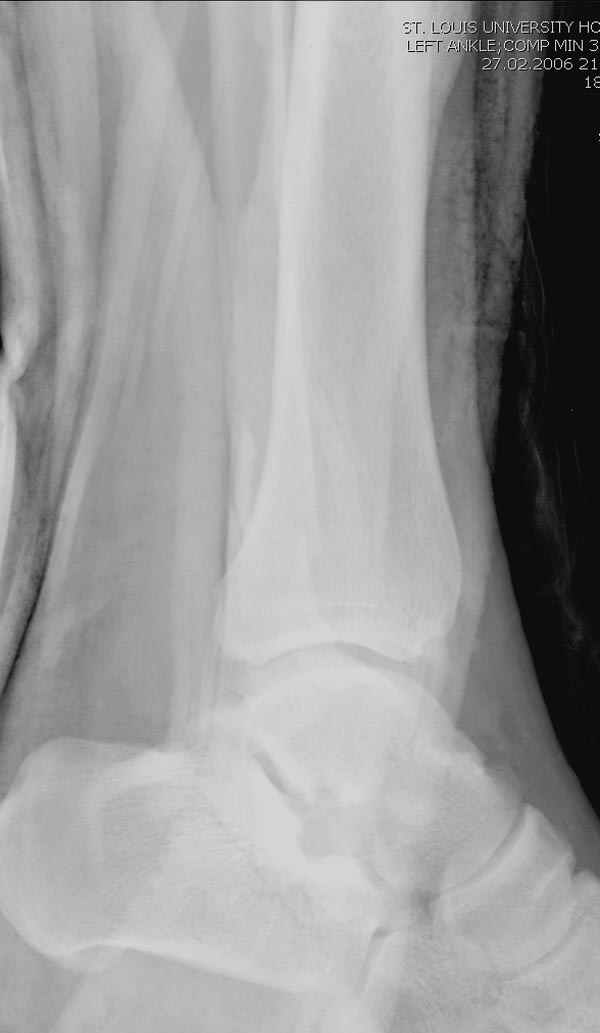

Тему неоднократно разбирали (см. архив), как всегда, недостаточны ренгенологические исследования - кроме прямого и боковых снимков, еще нужна косая ренгенограмма для определения ankle mortise, без мортиз снимка трудно определить высоту и ротацию малоберцовой. (снимки)

Ренгенология даст ответ как классифицировать перелом, на сегодня применяется классификация “Lauge Hansen fracture classification SER supination-external rotation или supination-eversion classification Danis

Weber А, В, С.”

Показания для фиксации: укорочения и ротация малоберцовой, особенно обращают внимание на любой подвывих таранной кости: неустраненый подвывих впоследствии приводит к раннему артрозу. Задний край фиксирует тогда, когда перелом составляет около 25% суставной поверхности голеностопного сочленения и смещение более 2мм.

По снимку ваш случай относится к Weber В, фиксацию производят восстановлением длины малоберцовой кости, под ренгеном (ЭП)контролем, для этого я предпочел бы латеральный доступ, остеотомия по линии перелома, удлинение малоберцовой засчет скоса линии остеотомии, компрессия “lag technique”по линии остеотомии и фиксацию провести латеральной пластиной. Отдельный задний доступ, остеотомия по линии перелома, репозиция и фиксация заднего края вашим предпочтительным методом: 3.5мм шурупом с шайбой или пластиной Antiglide Butress